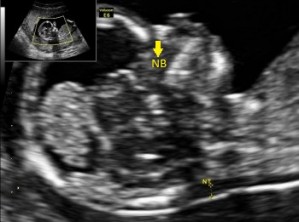

Kość nosowa - nosal bone (NB)

Fot.1. Ocena NB w przychodni PREGMED.